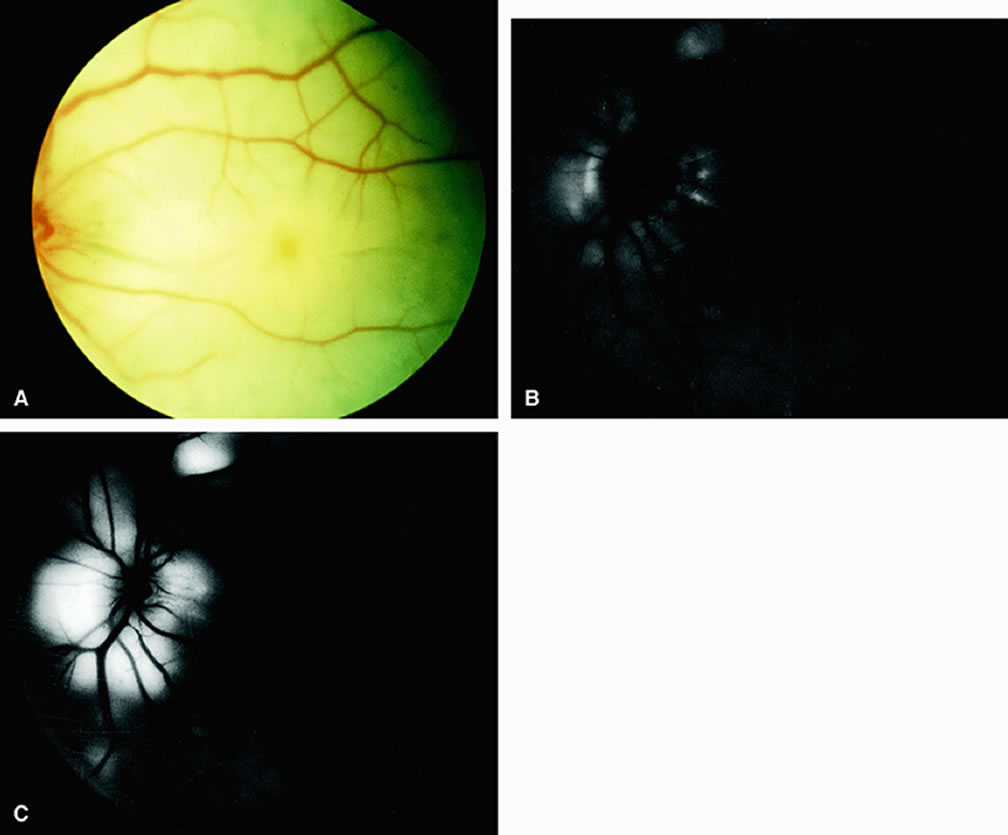

CENTRAL RETINAL VEIN OBSTRUCTION In eyes with central retinal vein obstruction, a thrombus is usually found in the obstructed vessel at or near the lamina cribrosa. Ophthalmoscopic signs of retinal vein obstruction include dilated tortuous veins, intraretinal hemorrhage, and ischemic retinal edema.10 Cotton-wool spots and a swollen optic disc are also often seen. Other less common signs of central retinal vein obstruction include vitreous hemorrhage and exudative retinal detachment. Several classifications have been employed to define central retinal vein obstructions. Central retinal vein obstructions can be divided into ischemic and nonischemic variants, depending in part on whether large areas of retinal capillary nonperfusion are present or absent. This classification is clinically useful because data from the Central Retinal Vein Occlusion Study Group11 and others12 suggest that laser panretinal photocoagulation can result in a regression of neovascularization of the iris, thereby preventing neovascular glaucoma. Compared with eyes that have the ischemic type, eyes with nonischemic central retinal vein obstruction typically have a visual acuity of 20/200 or better, relatively few cotton-wool spots, and less marked retinal hemorrhage.13 Fluorescein angiography usually shows an increased retinal arteriovenous transit time secondary to delayed retinal venous filling. Delayed retinal arterial filling can also be present. The retinal capillary bed is generally well perfused (Fig. 10). The retinal veins appear as a hypofluorescent silhouette against the bright choroid. There is also variable staining of the retinal veins and variable leakage on the angiogram. Approximately 20% of nonischemic central retinal vein occlusions will progress to ischemic central retinal vein occlusions. Ischemic central retinal vein obstructions generally reduce a patient's visual acuity to 20/200 or worse, most commonly to the counting-fingers or hand-motions range. Numerous cotton-wool spots and severe four-quadrant retinal hemorrhaging are often seen. Fluorescein angiography reveals confluent regions of retinal capillary nonperfusion (Fig. 11). Views of the posterior pole, as well as those of the four quadrants, may be necessary to demonstrate the capillary dropout. Magargal and associates12 quantitated the amount of retinal capillary nonperfusion in a posterior-pole 30-degree view in eyes with central retinal vein obstruction and calculated an ischemic index (area of retinal capillary nonperfusion/total area within the posterior 30-degree view). They found that when the index was 80% or greater, approximately 45% of eyes eventually developed rubeosis iridis and neovascular glaucoma. In some eyes with central retinal vein occlusion, determining the degree of retinal capillary nonperfusion with fluorescein angiography is difficult. Worsening visual acuity and progressive intraretinal bleeding indicate that an eye may be progressing toward a more ischemic state.14 In eyes with central retinal vein obstruction and a visual acuity of 20/200 or worse, performing fluorescein angiography at the initial visit can be useful to evaluate perfusion of the retinal capillary bed. The presence of a large amount of intraretinal blood in the posterior pole is not necessarily a contraindication to performing the study, particularly because these eyes are probably more prone to ischemia. The retinal blood generally diminishes rapidly anterior to the posterior pole, facilitating angiographic evaluation of the peripheral retina. BRANCH RETINAL VEIN OBSTRUCTION Branch retinal vein obstruction usually occurs at the intersection of a branch retinal artery with a vein. In general, the artery overlies the vein, and the two vessels share a common adventitial sheath at the crossing. Retinal hemorrhages are present along with cotton-wool spots (Figs. 12 and 13). These hemorrhages usually are reabsorbed over a period of months. Numerous microvascular abnormalities generally remain, and macular edema may be persistent. The Branch Retinal Vein Occlusion Study Group15 demonstrated that eyes with branch retinal vein obstruction and a visual acuity of 20/40 or worse may benefit from grid laser therapy to reduce macular edema. This study group recommended waiting at least 3 months after the onset of the obstruction to permit clearing of the retinal blood before performing fluorescein angiography. If the study shows that macular edema is responsible for the visual loss, grid laser therapy to the affected region within the vascular arcades can be considered. In cases in which foveal nonperfusion is responsible for the decrease in vision, laser therapy has not been shown to improve vision. Eyes with branch retinal vein obstruction and retinal capillary nonperfusion can develop neovascularization of the retina and/or disc. New vessels on the retina or optic disc intensely leak fluorescein dye, whereas larger collateral vessels on the optic disc or in the retina usually do not; thus, fluorescein angiography is helpful in differentiating between neovascularization and collateral vessels. Proper identification of posterior-segment neovascularization in eyes with branch retinal vein obstruction is important because scatter laser treatment in such cases has been shown to reduce vitreous hemorrhage in these eyes.16 In addition, fluorescein angiography can be used to identify the areas of retinal capillary nonperfusion requiring therapy. Scatter sector laser photocoagulation should be delayed until the onset of retinal neovascularization. |